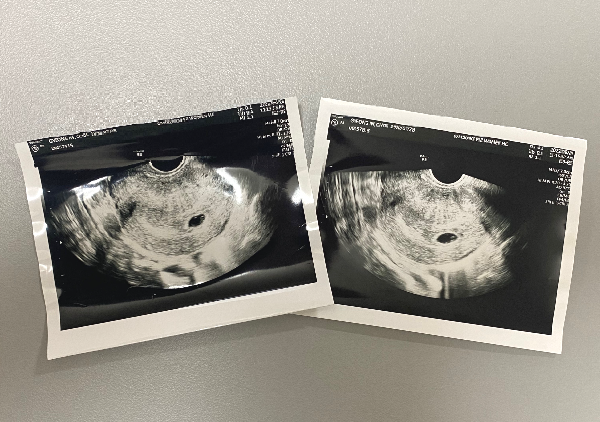

∨임신 5주차

- 질 초음파로 아기집 확인

그렇게 셋이서 함께 콩콩이와의 첫만남

5주 2일차에 아기집을 볼 수 있었다.

아기집을 보니 첫째를 처음 초음파로 봤던

4년전이 떠오르며 마음이 뭉클했다.

피검사 결과로 듣기만 했을 때보다 더 실감이 났다.